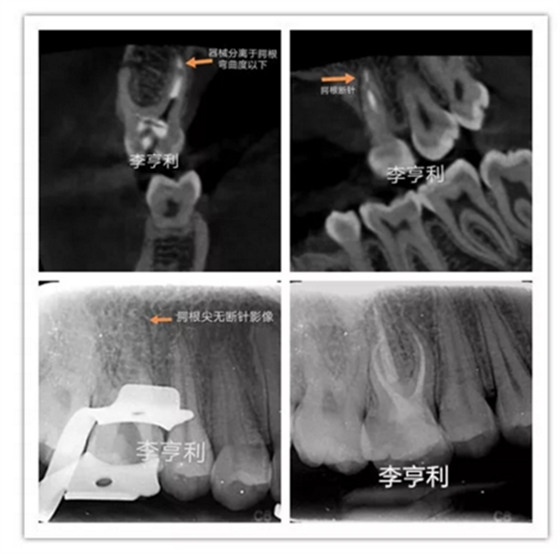

李亨利取出腭尖斷針的病例

在根管治療前,一定要充足地預(yù)估難度,謹(jǐn)記根管解剖,并且要熟悉自己臨床使用器械的設(shè)計、尺寸和參數(shù)。雖然說斷針本身并不影響治療效果,但往往都是因為患者的個人意愿,最后選擇取出斷針。如果難度超過術(shù)者自身的能力,就一定要轉(zhuǎn)診至??频难荔w牙髓醫(yī)生進(jìn)行處理。